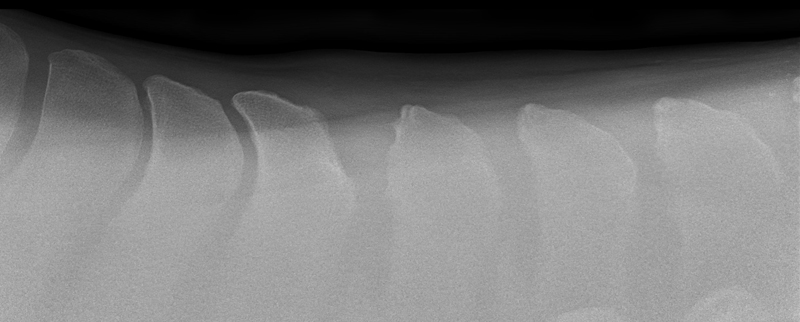

Kissing Spines, more scientifically known as impingement of the dorsal spinous processes, is a condition that has grown in relevance and impact throughout the last two decades with improved diagnostics and education. It’s hard not to feel a horse’s pain after taking just one look at an x-ray that indicates Kissing Spines. The condition can diminish athletic performance and render a horse unusable in severe cases, while other cases with the ugliest x-rays can experience no pain or performance implications. While still shrouded in some level of mystery, Kissing Spines is known to be conformational and most likely genetic. When spinous processes are conformationally close together they will inevitably contact, with that continual contact causing the modeling changes that are classically seen on radiographs.

Though Kissing Spines can be seen clearly in diagnostic imaging, truly understanding the nuances of the condition and how it can vary patient-to-patient is where things become less well-defined. Dr. Cliff Honnas, equine veterinarian, surgeon and founder of the widely respected Texas Equine Hospital in Bryan, Texas, is a sought-after authority figure in all things related to this condition, especially concerning its surgical treatment. “Kissing Spines is a condition where the dorsal spinous processes are too close together,” he explains simply. “These are the bones that make up the backbone of the horse directly underneath the saddle.” Normal horses should typically have a five millimeter or larger space between those bones, depending on the breed and size of the animal in question. In Kissing Spines cases, however, that space can be minimally to drastically narrowed until those bones are close together, touching or overriding.

While there are numerous conditions impacting the equine back, the diagnosis of Kissing Spines has increased fairly dramatically in recent years thanks to improved diagnostic techniques coupled with a greater focus on veterinary education. “Depending on who you choose to believe in the literature, Kissing Spines along with dorsal articular facet arthritis will account for 50 to 70 percent of orthopedic back problems,” says Dr. Kent Allen, sports medicine practitioner, founder of Virginia Equine Imaging, FEI Olympic-level veterinarian, current Vice President and Executive Director of ISELP and Chairman of the USEF (United States Equestrian Federation) Veterinary Committee. “The horse, which of course has a horizontal back as opposed to a human’s vertical back, doesn’t have disk problems like we do but rather has bony orthopedic problems that impact the way they bend, extend and jump, such as Kissing Spines and arthritis of the dorsal articular facets,” explains Dr. Allen. “In terms of Kissing Spines specifically, its location is most commonly from the base of the withers back to the thoracolumbar junction, from T16 back to L2-3. In contrast, arthritis of the articular area will often occur further back, about three inches forward to three inches behind the rear of an English Saddle.” While the general location and disease process have become more solidified, the clinical presentations exhibited by affected horses are wide-ranging and can create significant diagnostic and treatment challenges for veterinarians.

A condition where the dorsal spinous processes are too close together. Typically horses have about a five millimeter space between those bones; however, in Kissing Spines cases, that space is narrowed until those bones are close together, touching or overriding.

While the clinical signs of Kissing Spines can be ambiguous, Dr. Allen is quick to point out that not all horses with radiographic evidence of the condition display outward signs. “It's often a question of when this condition presents or if it presents. If we’re talking about a western pleasure horse or a horse that doesn’t ever jump over 2 feet 6 inches in its life, the animal may have Kissing Spines and never present. A look at the data on hundreds of horses with back pain revealed that the average age of presentation of back pain was about 6.5-years-old.”

While horses may be genetically predisposed to Kissing Spines and present clinical signs on an x-ray as early as 2-years-old, there are a great number of factors that go into determining if that horse will ever become clinical, including its level of training and specific discipline. Horses performing a sport that requires a high amount of flexing and bending of the back will oftentimes have increased odds of developing clinical symptoms of Kissing Spines in comparison to low-impact or more leisure-based sports — think of a cutting horse versus a horse primarily used on the trail. “A common situation is that we’ll see a horse come in for a pre-purchase exam, and since we’ll routinely do a back x-ray now, we’ll often see some degree of Kissing Spines,” says Dr. Honnas of a frequent and tough place that equine veterinarians find themselves in with potential buyers. “This could mean that space between those bones is reduced but very often not actually touching or overriding. We can also see horses that have tremendous Kissing Spines on an x-ray, but clinically are virtually normal and have no history of back pain. It makes it very difficult to decide on a pre-purchase exam what to recommend to the potential buyers in terms of their risk. This can be a top-end horse, doing its job well and with no disability. We’ll pick up Kissing Spines to some degree on the x-ray, and it’s impossible to state with certainty that horse’s risk of developing symptoms in the future.”

Following a thorough whole-body physical examination and a more specialized motion evaluation, the next step in a suspected case of Kissing Spines is to confirm the diagnosis with imaging. Drs. Honnas, Story, Williams and Allen are all significant proponents of the importance of those initial examinations prior to performing imaging. “I tell my clients, ‘I can x-ray your horse's back and look for things like Kissing Spines, but that could be just a tip of the iceberg,’ ” says Dr. Williams. “That comprehensive evaluation is absolutely necessary to form a complete picture.”

There are two primary diagnostic imaging methods that deliver the clearest picture — literally and figuratively — when dealing with a potential Kissing Spines case. “I teach combined imaging using x-ray and ultrasound to look at as much of the tissue as possible,” says Dr. Williams of his approach. While Kissing Spines can oftentimes appear clearly using x-ray alone, the use of this combined imaging approach delivers the most definitive diagnosis possible. “Ultrasound is the most sensitive tool to observe surface detail. It reflects off of bone. You can't see through it, but if the bone surface is uneven, it will tell you that. On an x-ray or a radiograph you can’t pick that up unless you get the perfect view,” says Dr. Williams of one reason he brings ultrasound into the equation. Another attribute of ultrasound is its ability to look at the supraspinous ligament, multifidus muscles and the facet joints, which are placed further down at the base of the spinous processes. “I talk about ultrasound surveys,” says Dr. Williams. “I don't just look with the ultrasound, then find something and walk away. I survey the back from the withers all the way back through the lumbar region. This gives me all of the information, and I can then better determine whether the horse has Kissing Spines alone, if the case is surgical and if there’s something else at play in addition to the Kissing Spines.”